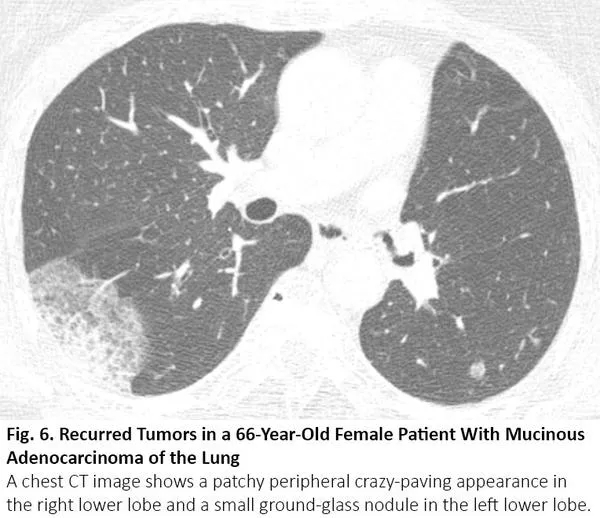

肺癌CT通常表现为结节或肿块,但有时也可表现为空洞。浸润性黏液腺癌是一个著名的例子,可呈现实性病变,伴或不伴磨玻璃样影,类似肺炎。腺癌的特定亚型,包括伏壁式、腺泡型和乳头型为主的腺癌,CT图像可呈现毛玻璃样阴影的区域。16当这些病变发生在肺部多处,其胸部CT可能与COVID-19有相似(图6)。如果既往的胸部CT显示这些病变已经持续存在,则可以与COVID-19区分。

图6. 一位66岁粘液性肺腺癌患者肿瘤复发后的胸部CT